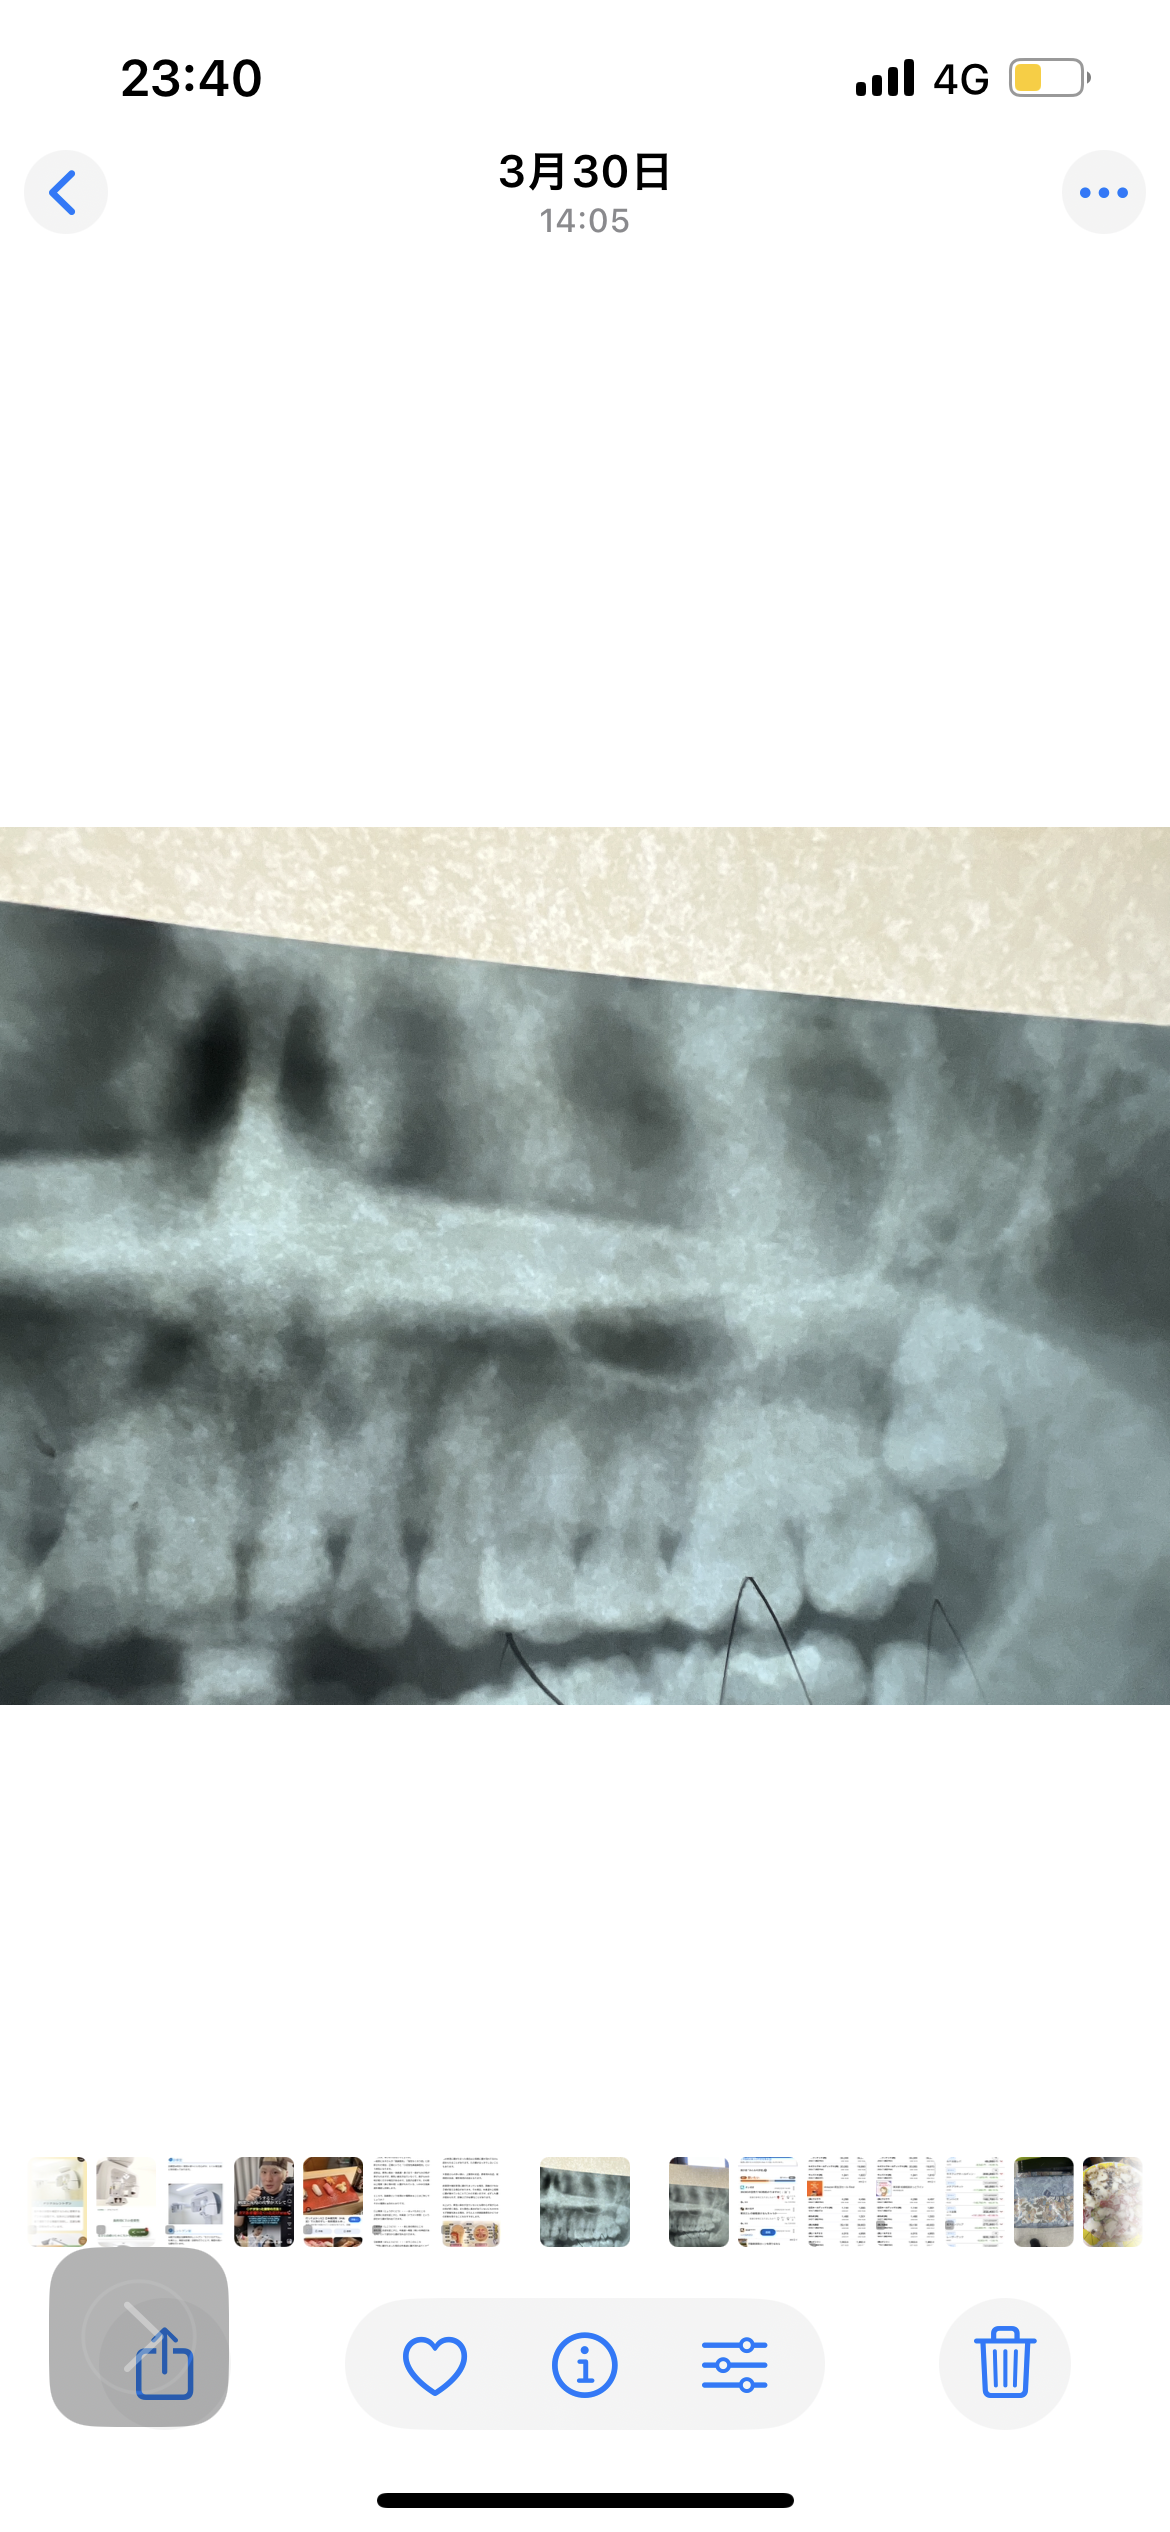

矯正終了時に頂いたレントゲンです。

埋伏智歯があります。

片側から後鼻漏や鼻詰まりがありますが、歯性上顎洞炎の可能性はありますか?

埋伏している親知らずがあるようですが、それと鼻の症状、頭痛との関連はあまりないように思います。